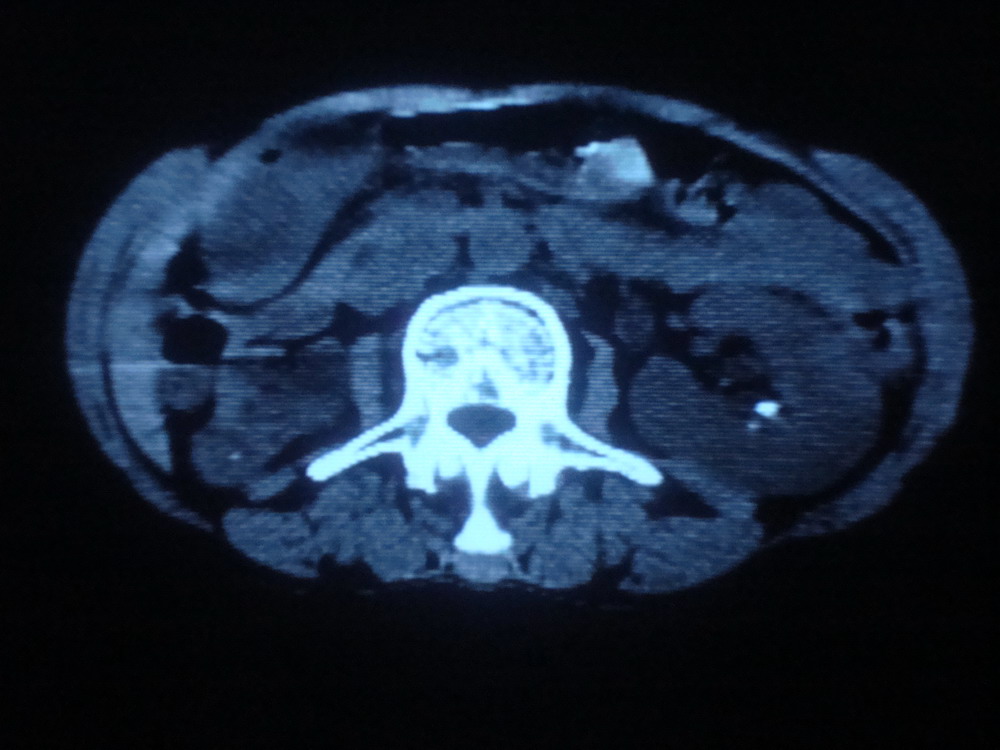

以下是引用卜一在2009-4-1 19:39:00的发言:[br]右肾发育不全、结石、积水并感染可能;左肾结石,代偿性增大。支持!

以下是引用随缘的人在2009-4-1 20:42:00的发言:[br]右肾发育不全、结石、积水并感染可能;左肾结石,代偿性增大。支持!